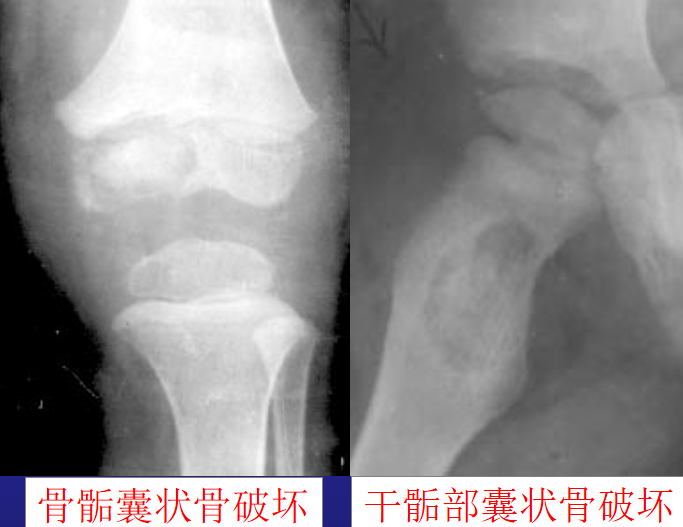

X线表现:1、急性期:关节囊肿胀、关节间隙增宽,关节囊和韧带破坏可致关节半脱位及脱位;2、病变进展迅速,关节软骨破坏,关节间隙狭窄;3、肉芽组织增生,破坏软骨下骨,承重部分出现早和明显;4、愈合期骨质增生硬化,严重时骨性强直

(1)X线平片:关节囊肿胀;关节间隙增宽,随后则关节间隙狭窄,承重面骨质破坏; 半脱位;骨性关节强直;(2)CT:肿胀、积液、骨端破坏;(3)MRI:滑膜炎、积液、软骨破坏、软组织受累范围

1、关节肿胀;2、关节间隙变窄;3、关节面骨破坏;4、骨质疏松

1、骨质破坏;2、关节腔内大量积液;3、关节间隙不窄

关节结核X线平片

1、骨型:继发于骺、干骺端结核或滑膜型

2、滑膜型:血行感染,常见大关节。

a、关节囊肿胀;间隙略宽;骨质疏松;患侧骨骺出现早和略大

b、关节非承重面骨质虫噬状破坏

c、关节间隙狭窄出现较晚;冷性脓肿、瘘管;d、纤维性强直